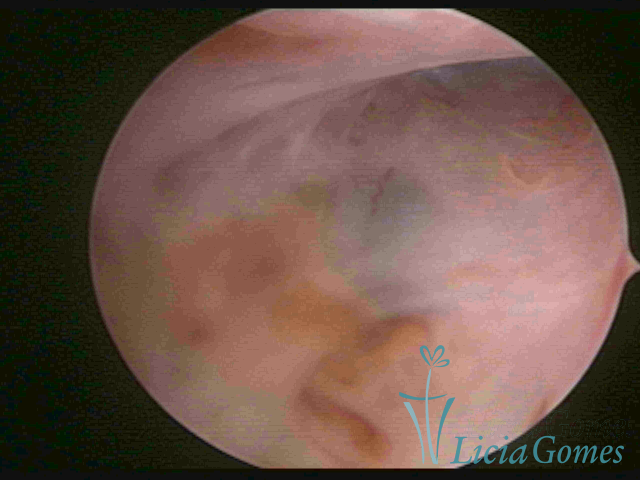

ADENOMYOSIS

The presence of endometrial tissue on the muscular layer of the uterus.

Video hysteroscopy allows diagnosing the lesions next to the superficial myometrial layers next to the endometrium, allowing the view of in situ, purplish, or chocolate brown lesions.